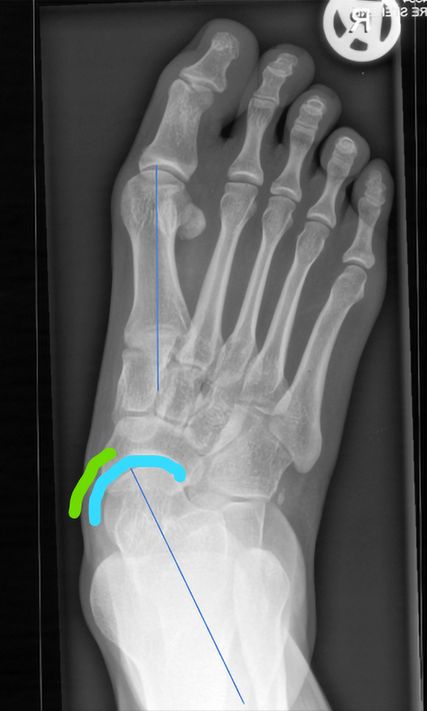

Abb. 1: Präoperativ: blaue Linie = Talus-MT1-Winkel; gebogene Linien: „talar head uncoverage“

Die d.p. Aufnahme zeigt das Ausmaß der Abduktion des Vorfußes, die talonaviculare Überdeckung („talar head uncoverage“, Abb. 1).3 Degenerative Veränderungen der einzelnen Gelenke werden beurteilt.